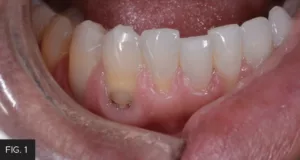

This case report of restorations on teeth #27 and #28 illustrates the extent to which decay can exist subgingivally associated with existing Class V resin restorations. (FIG. 1) To gain access for caries removal and provide ideal conditions for the placement of a bonded full-thickness restoration, the tissue must be either repositioned or removed. The options to manage the gingival tissue involve either a full-thickness flap surgical approach to reposition the tissue or a more conservative option with an electrosurgery unit or a laser. The decision in this case was to use the Bluewave™ Soft Tissue Diode Laser (Clinician’s Choice®), which is a portable 5W 810nm soft tissue laser. The 810nm wavelength is highly absorbable by hemoglobin and melanin, resulting in minimal bleeding, and allows for rapid healing of the wound. The Bluewave diode laser is very cost-efficient, lightweight, battery operated, and portable to easily move between operatories. The unit occupies a small footprint of counter-space and the laser handpiece is held securely in place with a magnetic cradle for increased protection against accidental dislodgement and breakage.